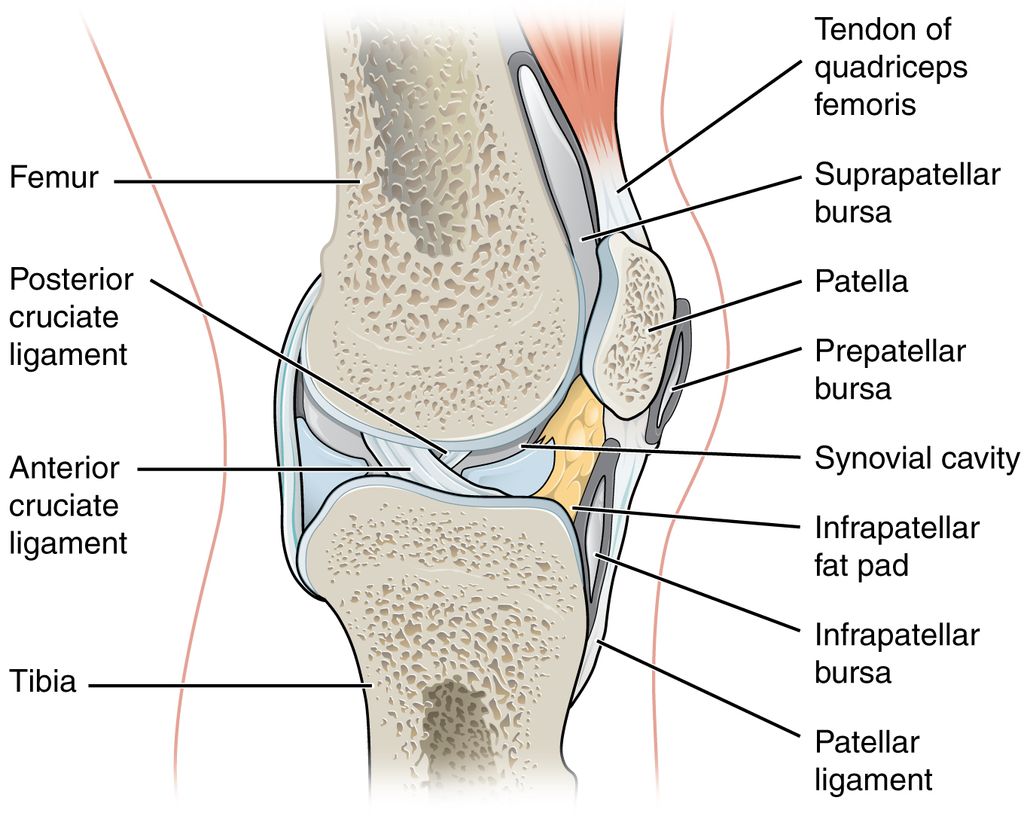

The knee joint is one of the most complex joints in the human body, consisting of bones, cartilage, tendons, and ligaments. Knee ligaments play a crucial role in providing stability and support to the joint. The four main knee ligaments include the anterior cruciate ligament (ACL), posterior cruciate ligament (PCL), medial collateral ligament (MCL), and lateral collateral ligament (LCL). These ligaments work together to control knee movement and prevent excessive rotation and translation.

At the core of knee joint stability are the ligaments that connect the bones of the knee together. The knee joint is comprised of four major ligaments that connect the femur to the tibia and fibula: the anterior cruciate ligament (ACL), the posterior cruciate ligament (PCL), the medial collateral ligament (MCL), and the lateral collateral ligament (LCL).

Anatomy of Knee Ligaments

The ACL and PCL are located inside the knee joint, while the MCL and LCL are located on the outside of the joint. These ligaments are made up of collagen and elastic fibers that provide strength and stability to the knee joint. The ACL is responsible for preventing the tibia from moving too far forward, while the PCL prevents the tibia from moving too far backward. The MCL and LCL work together to prevent the knee from moving side to side.